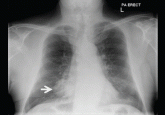

ArticleA 78-year-old smoker with an incidental pulmonary massAuthor:Charlotte Cash, FRCRPublish date: August 1, 2014His age, smoking history, and findings on radiography raised the concern of lung cancer.Read More